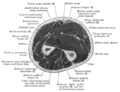

مقطع مستعرض في الساعد يظهر فيه عظم الكعبرة وعظم الزند.